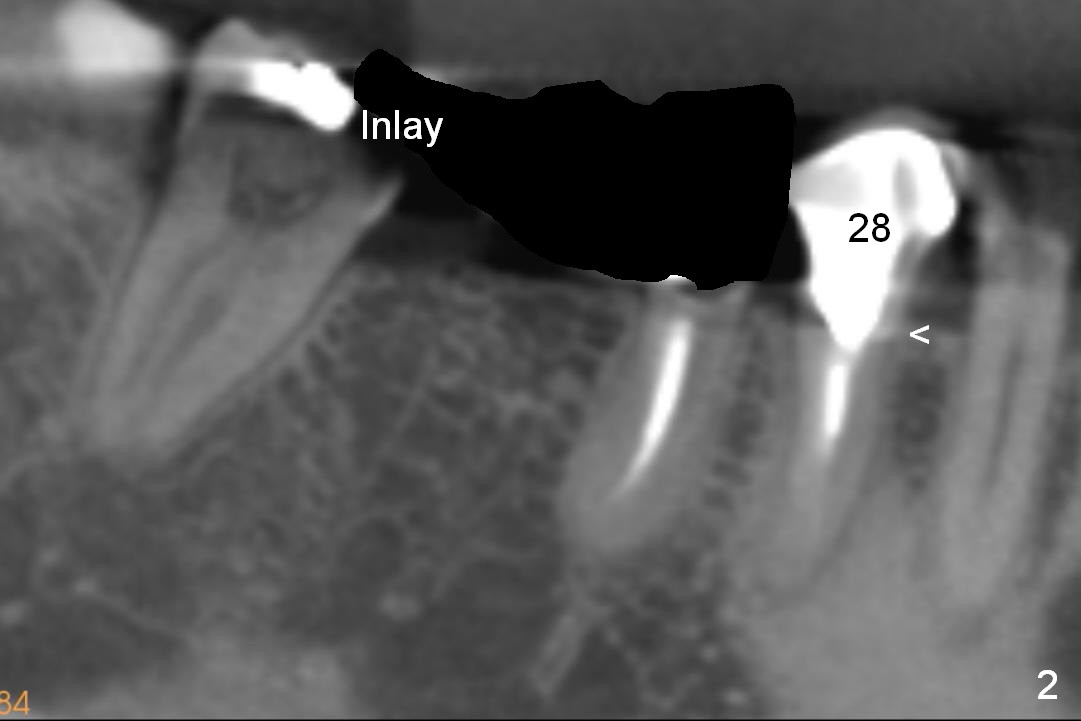

The posterior 3-unit should be able to dislodge (Fig.2). Check whether there is the similar lesion associated with #28 (<). The tooth #31 should be afforded not to be restored, since there is a small inlay prep mesially.